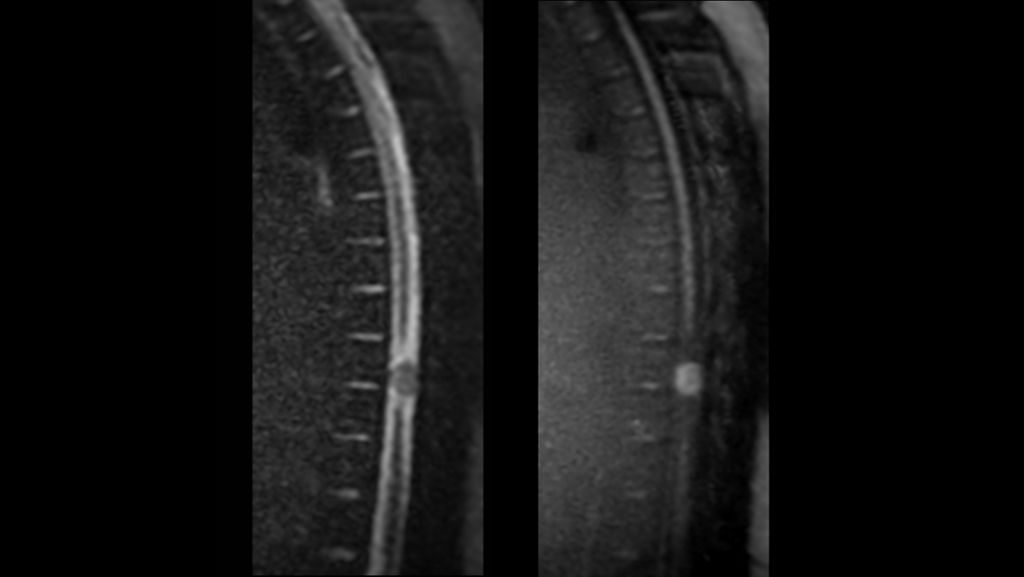

• DWI TSE (b0 and b400)

DWI TSE (b0 and b400)

DWI TSE allows diffusion imaging with excellent signal-to-noise ratio and sharpness with reduced geometric distortion¹, especially in challenging anatomies.

¹Compared to DWI EPI